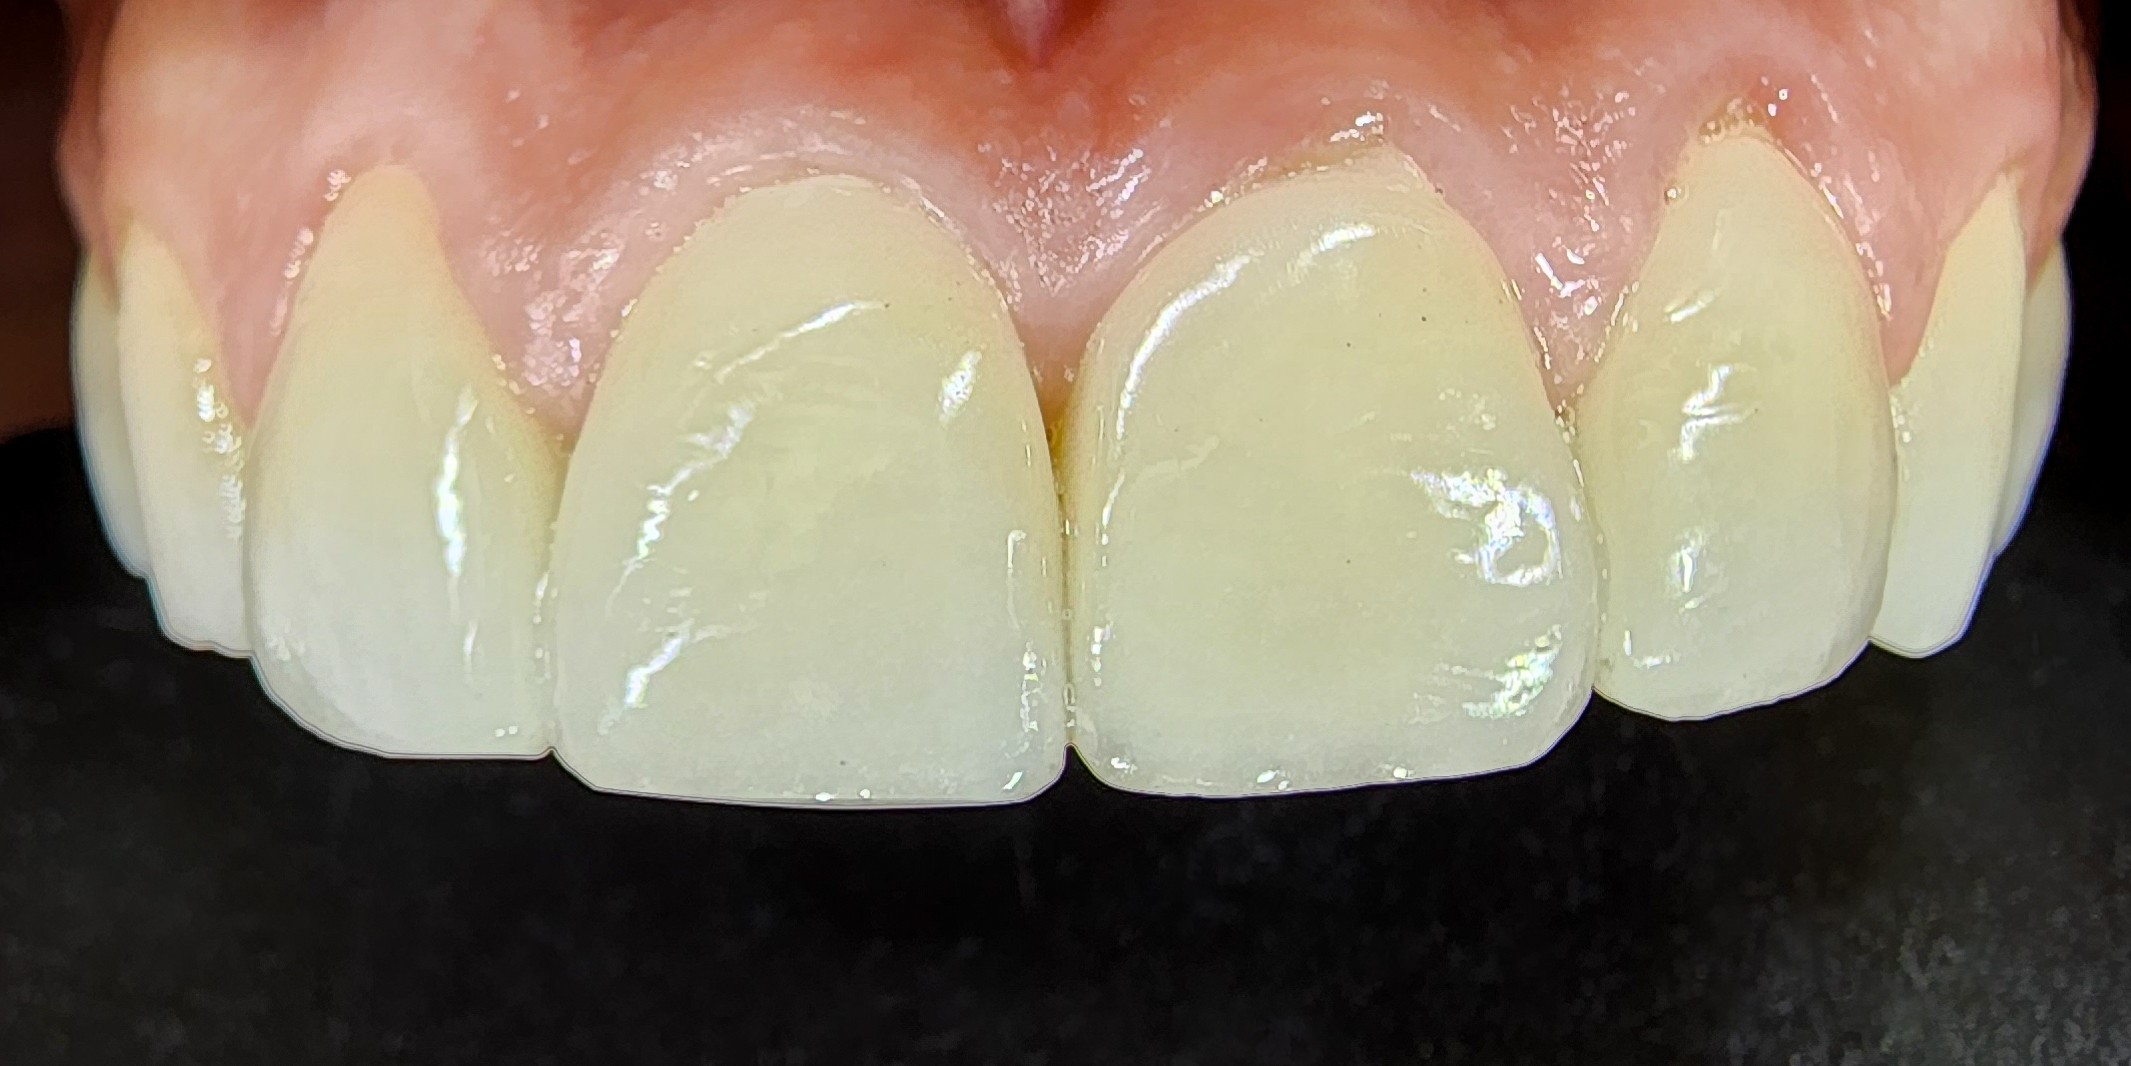

Bonding porcelain veneers, or as they go by their foreign name – laminate veneers, requires a lot of technical and medical skill, a lot of experience, perfectionism and an artistic eye. The transition area between the veneers and the gums is where millions of bacteria accumulate, causing gingivitis, bleedings and pain. The gums look swollen and unsightly. It is imperative to maintain good gum health to get a natural-looking and beautiful result. The goal is to achieve a beautiful and glamorous smile without letting others see that we have applied porcelain veneers. That is why one must not compromise when choosing a dentist.A cost-based compromise almost always leads to double work and double costs. The first time, people pay a low price, and the second time, they pay the right price to replace the porcelain veneers. A natural, healthy, white and beautiful smile is Dr. Gilad Fiskus’s signature.